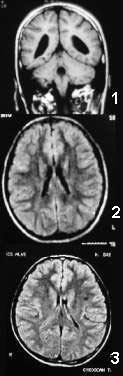

No exemplo 1 da figura, a microcefalia foi causada por Toxoplasmose, está

acompanhada de redução de substância branca e Hipoplasia

do Corpo Caloso. No exemplo 2, está associada a uma Assimetria

Ventricular, enquanto que no exemplo 3, aparece junto com Gliose.